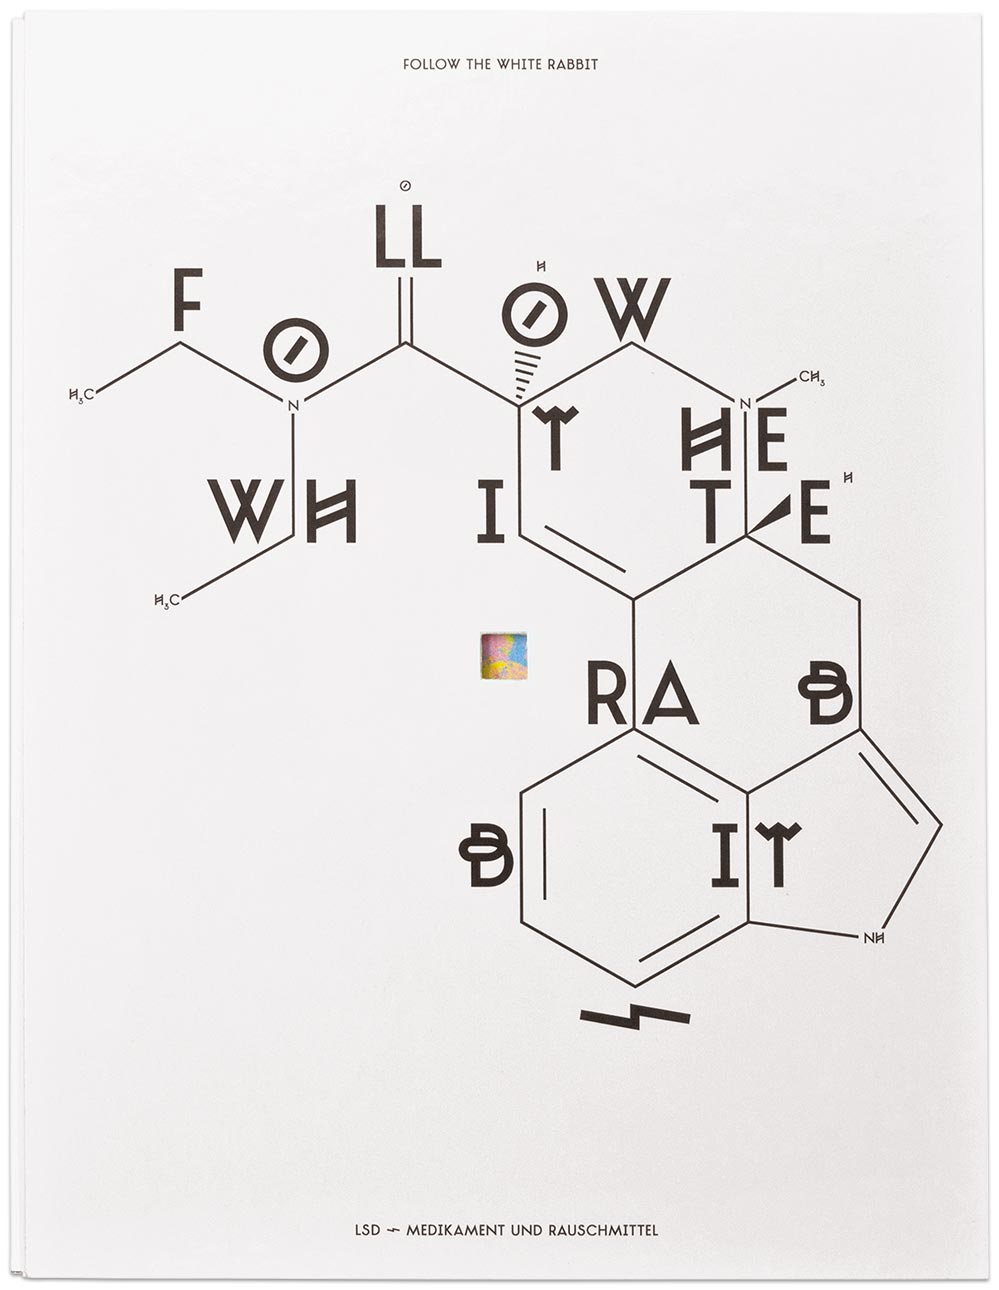

Follow The White Rabbit

ID # 23816

Fachhochschule Mainz, DE

professor : Isabel Naegele

Sara Ellinger

contact :

www.saraellinger.de